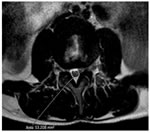

CASE 3

T2 W AXIAL IMAGE AT L3-4 LEVEL SHOWING REDUCED THECAL SAC AREA BUT THERE IS NO COMPRESSION SUGGESTIVE OF PROMINENT EPIDURAL FAT PAD. THERE IS ALSO EVIDENCE OF LIGAMENTUM FLAVUM HYPERTROPHY AND FACETAL ARTHROPATHY

POST CONTRAST T1W CORONAL IMAGE SHOWING ENHANCEMENT OF L3 AND L4 VERTEBRAL BODIES ALONG WITH L3-L4 INTERVERTEBRAL DISC ENHANCEMENT AND PARAVERTEBRAL SOFT TISSUE ENHANCEMENT ON THE LEFT SUGGESTIVE OF SPONDYLODISCITIS.

POST CONTRAST T1W AXIAL IMAGE SHOWING ENHANCEMENT OF PARAVERTEBRAL AND PARASPINAL REGION ON THE LEFT AT THE LEVEL OF L4 VERTEBRAL BODY